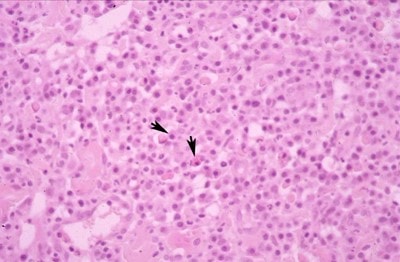

Examen histopathologique de biopsies cutanées (Photos 3 et 4)

L’analyse histopathologique révèle un pattern de dermatite nodulaire avec un infiltrat composé quasi-entièrement de plasmocytes, certains d’entre eux contenant des inclusions éosinophiles correspondant à des immunoglobulines (corps de Russel). Dans ce contexte clinique, ce tableau histopathologique est fortement évocateur de pododermatite plasmocytaire.

Photo 3

Photo 4